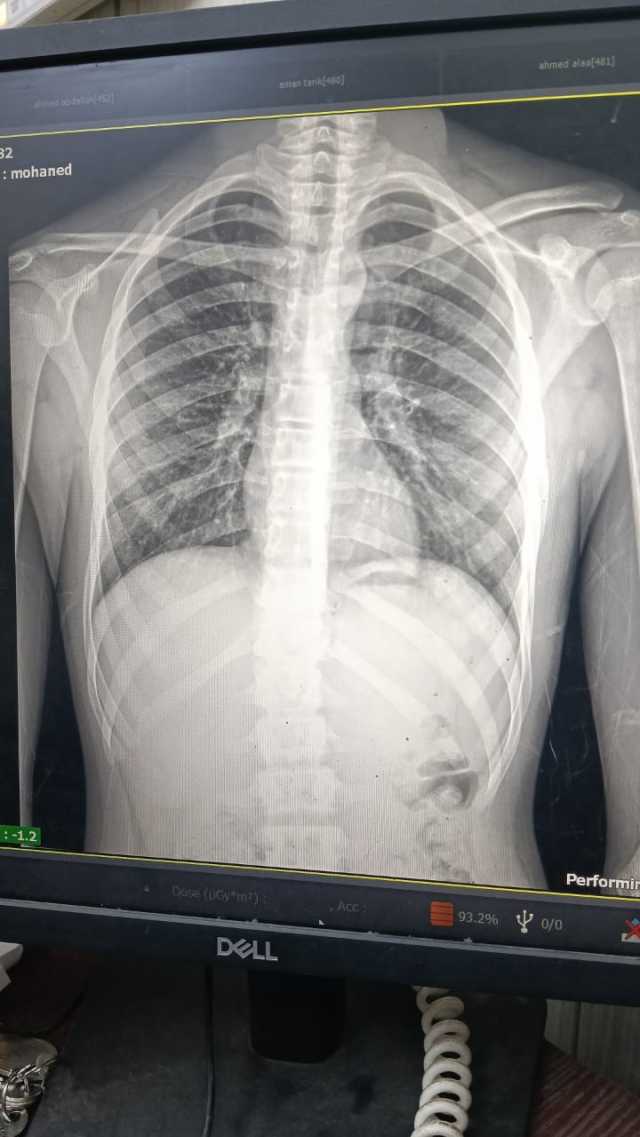

وتعود أحداث الواقعة حينما تلقت الأجهزة الأمنية بمديرية أمن الغربية إخطارا من مأمور قسم شرطة ثان طنطا يفيد بورود بلاغ من شرطة النجدة حول واقعة إصابة صغير يدعي "مهند شعبان " 15 سنة علي يد آخرين في مشاجرة بالأسلحة البيضاء بنطاق منطقة نايف عماد بنطاق دائرة القسم.